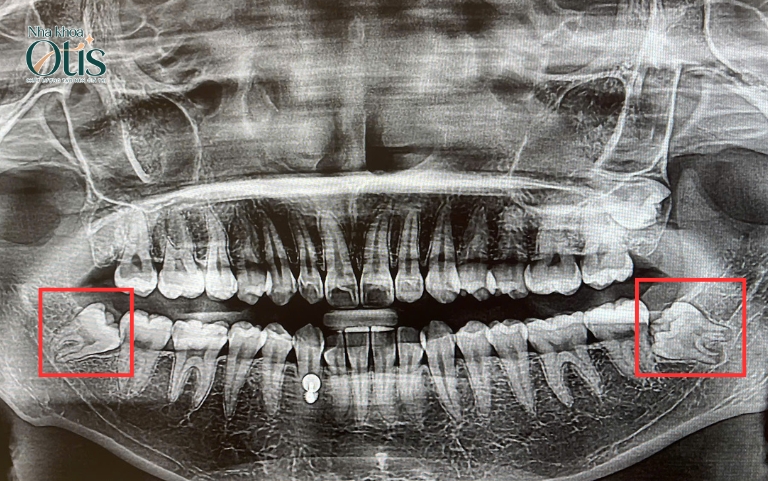

Răng khôn mọc lêch hoặc mọc ngầm

Vì răng khôn mọc sau, không còn không gian nên răng thường mọc lệch hoặc mọc ngầm. Khi răng mọc nghiêng, thường đâm vào răng số 7, tạo lực đẩy làm yếu chân răng, gây đau kéo dài và tăng nguy cơ sâu kẽ răng.

Đối với nhổ răng khôn mọc ngầm, do phần răng nằm dưới nưới có thể gây sưng viêm, nhiễm trùng mô mềm hoặc hình thành nang quanh chân răng. Đây đều là những tình trạng không thể tự khỏi và dễ tiến triển nặng hơn nếu không xử lý kịp thời.